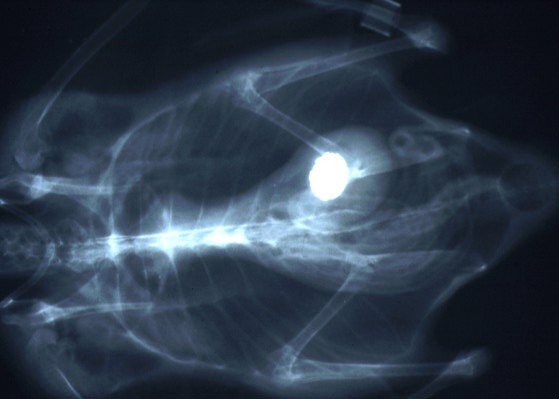

Radiograph of a 6-month-old eider duck with a metal foreign object in the ventriculus. (31K)

Signalment: 6-month-old American eider duck (Somateria mollisima dresseri) male, 1.4 kg.

History: Noted to be depressed (on exhibit); radiograph revealed penny in ventriculus; treated with itraconazole, fluids, baytril, and calcium versonate. There was no improvement over next 10 days. The penny was surgically removed. The duck died 24 hours later.

The penny removed from the ventriculus of this duck was too severely eroded to read the year of minting, but the gray metallic center indicates that it is composed primarily of a high zinc alloy with a thin coating of copper as are all pennies minted after 1982 (1). Presumably, the duck ingested the penny from a pond in the exhibit, where it may have been tossed by a zoo visitor. Pancreatic fibrosis and necrosis have been associated with zinc toxicity in ruminants (2), chickens (3,4) and ducks (5,6).